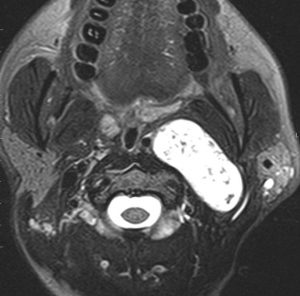

症例:頸静脈孔より下の深頸部のもの:副咽頭間隙腫瘍

左頸静脈孔の下の迷走神経節から発生したものです。ごく軽い飲み込み辛さだけが症状でした。

内頚動脈を強く圧排して,外形動脈からはかなり豊富な血流が流入しています。頭頸部外科で顎骨を割るような手術を計画されていました。

でも,右側の画像で見るような角度から,小さな頸部の皮膚切開だけで,胸鎖乳突筋だけを乳様突起から外して翻展して摘出できました。内部からほじくるように摘出すれば症状悪化はないのですが,周囲軟部組織から切断して剥離しようとすると厳しい嚥下障害と嗄声になります。

手術で全摘出しましたが嚥下障害などはでませんでした。普通のおとなしい神経鞘腫ですから再発はありません。